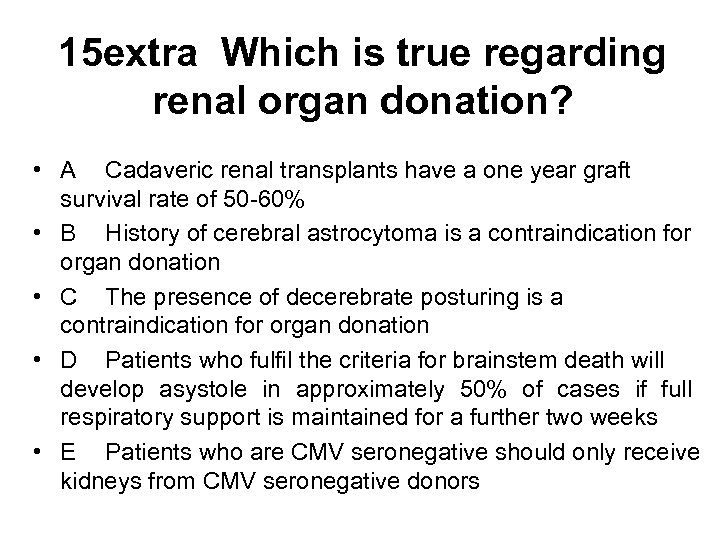

15 extra Which is true regarding renal organ donation? • A Cadaveric renal transplants have a one year graft survival rate of 50 -60% • B History of cerebral astrocytoma is a contraindication for organ donation • C The presence of decerebrate posturing is a contraindication for organ donation • D Patients who fulfil the criteria for brainstem death will develop asystole in approximately 50% of cases if full respiratory support is maintained for a further two weeks • E Patients who are CMV seronegative should only receive kidneys from CMV seronegative donors

15 extra Which is true regarding renal organ donation? • A Cadaveric renal transplants have a one year graft survival rate of 50 -60% • B History of cerebral astrocytoma is a contraindication for organ donation • C The presence of decerebrate posturing is a contraindication for organ donation • D Patients who fulfil the criteria for brainstem death will develop asystole in approximately 50% of cases if full respiratory support is maintained for a further two weeks • E Patients who are CMV seronegative should only receive kidneys from CMV seronegative donors

15 extra Which is true regarding renal organ donation? • A Cadaveric renal transplants have a one year graft survival rate of 50 -60% • B History of cerebral astrocytoma is a contraindication for organ donation • C The presence of decerebrate posturing is a contraindication for organ donation • D Patients who fulfil the criteria for brainstem death will develop asystole in approximately 50% of cases if full respiratory support is maintained for a further two weeks • E Patients who are CMV seronegative should only receive kidneys from CMV seronegative donors

15 extra Which is true regarding renal organ donation? • A Cadaveric renal transplants have a one year graft survival rate of 50 -60% • B History of cerebral astrocytoma is a contraindication for organ donation • C The presence of decerebrate posturing is a contraindication for organ donation • D Patients who fulfil the criteria for brainstem death will develop asystole in approximately 50% of cases if full respiratory support is maintained for a further two weeks • E Patients who are CMV seronegative should only receive kidneys from CMV seronegative donors